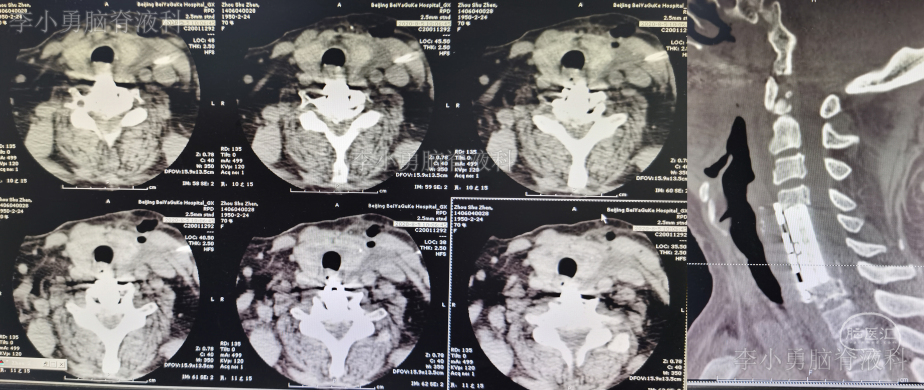

2020年8月4日(即第一次行前路颈5-6椎间盘切除椎间植骨融合内固定术后第114天),再次行颈椎前路颈5、颈6锥体次全切、人工锥体钛板螺钉内固定术,2020年8月5日(即第二次颈椎病术后第1天)复查颈椎平片及颈椎CT示椎管狭窄解除,人工椎体位置良好(图-6、图-7)。

图-7:2020年8月5日颈椎CT